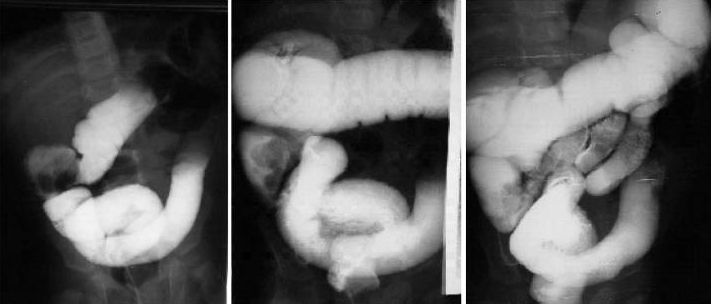

• Air or contrast enemas (under ultrasound guidance) can successfully reduce the intussusception in 80-90%.

• If the contrast enema fails to reduce the intussusception, or if the child has signs of peritonitis or pneumoperitoneum, operative reduction is indicated.